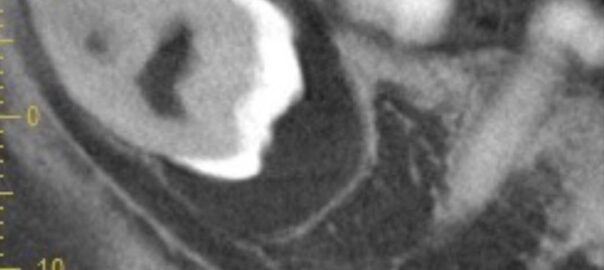

- 2024/04/13 嚢胞が疑われる親知らず

こんにちは、静岡市駿河区にある歯科医院、小嶋デンタルクリニックです。 親知らずの抜歯を希望されて来院された患者様。 完全埋伏だけで腫脹することがあるとのこと。完全埋伏だけど腫脹するの?と思う方 … 続きを読む 嚢胞が疑われる親知らず

→ 続きを見る